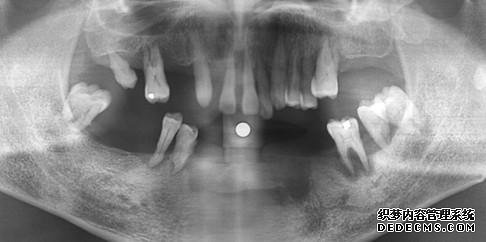

治疗方案:健民男科的种植医生通过系统的男科检查,诊断朱先生为重度牙周病及上下牙列缺损。朱先生自述,无既往病史,有对金属过敏经历。

拟定制治疗计划:保留左上3和右上3,拔除其余男科,采用种植牙的方式进行修复。上颌综合条件较好,采用即拔即种的种植方式,下颌条件稍差,因炎症而使骨缺损严重,故决定三个月后再进行种植。与患者协商后,患者接受该治疗方案。

朱先生半年后到院复查的全景片,恢复效果非常好。朱先生表示,都半年多了,没有产生任何金属过敏反应,也没有任何不适感或副作用,种植牙不仅恢复了正常的咀嚼功能,而且外观与真牙较为相似,难辨真假,甚至比真牙还要好用。